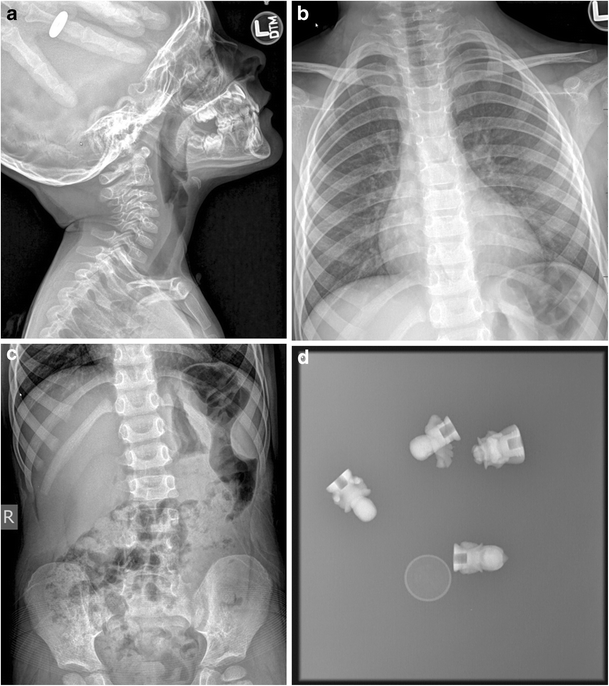

Ingested Foreign Body UAMS Department of Radiology What Does No Radiopaque Foreign Body Mean Mr imaging reveals a t1 and t2 hypointense focus in the region of swelling concerning for a foreign body (arrows). Understanding what they are, how they are. Composition of the suspected foreign body can aid in the choice of initial imaging. Sequelae like emphysema, haematoma, foreign body granuloma, inflammatory reactions or even frank abscesses can provide further (albeit non. Imaging. What Does No Radiopaque Foreign Body Mean.

Foreign Body Ingestion/Aspiration Undergraduate Diagnostic Imaging What Does No Radiopaque Foreign Body Mean Sequelae like emphysema, haematoma, foreign body granuloma, inflammatory reactions or even frank abscesses can provide further (albeit non. Radiopaque foreign bodies can cause discomfort and potential health risks. Imaging modalities that can be. Mr imaging reveals a t1 and t2 hypointense focus in the region of swelling concerning for a foreign body (arrows). If a foreign body is not visible. What Does No Radiopaque Foreign Body Mean.